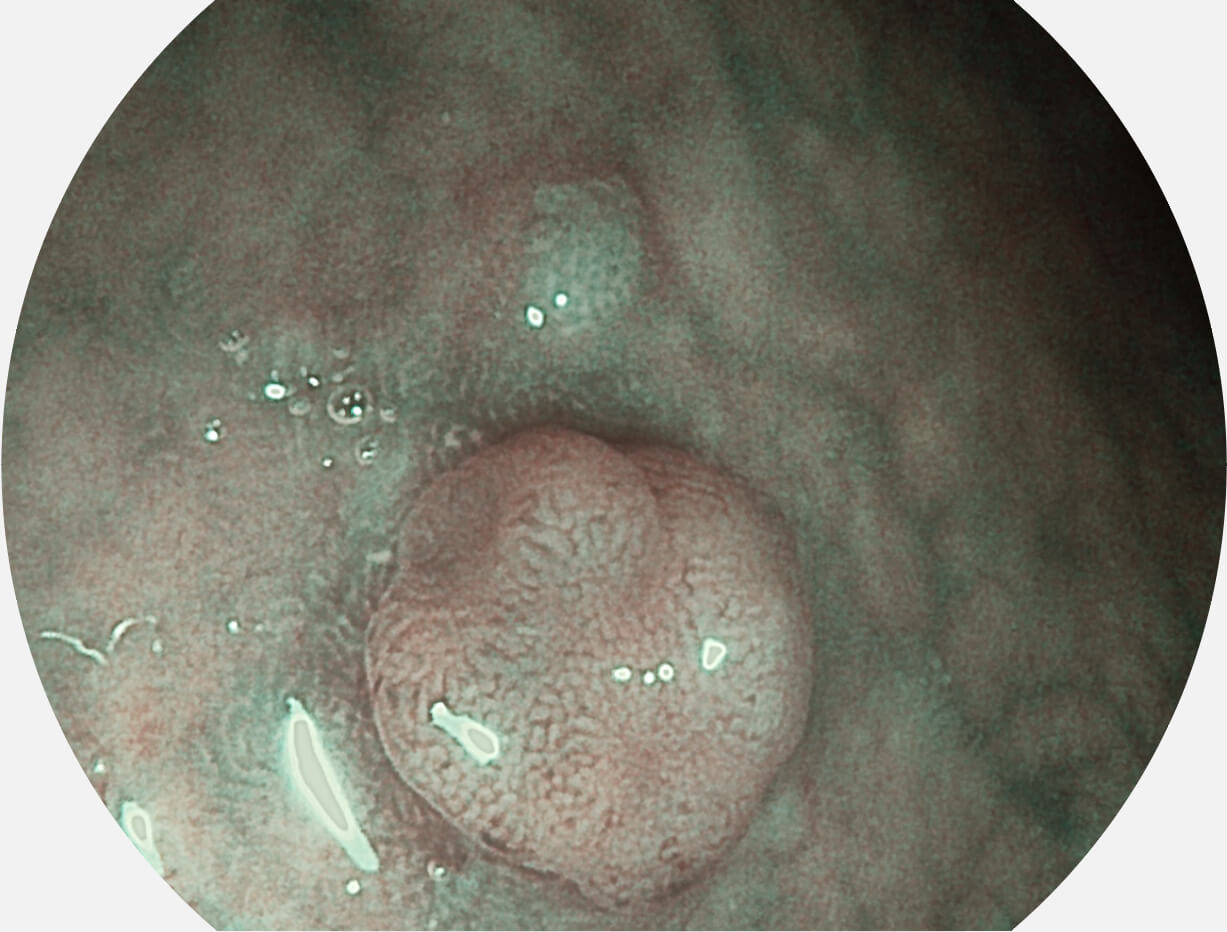

图像具有高亮度、高黏膜血管颜色对比度的特点,且不改变粘液、食物残渣、粪便的基本颜色,可在中远景下进行观察,助力消化道早期疾病的诊断。

白光图像

SFI图像

采用光路合束技术,光谱自由度高,实现了更丰富的照明模式,染色模式SFI及VIST,从远景到近景,助力消化道早期疾病诊断。